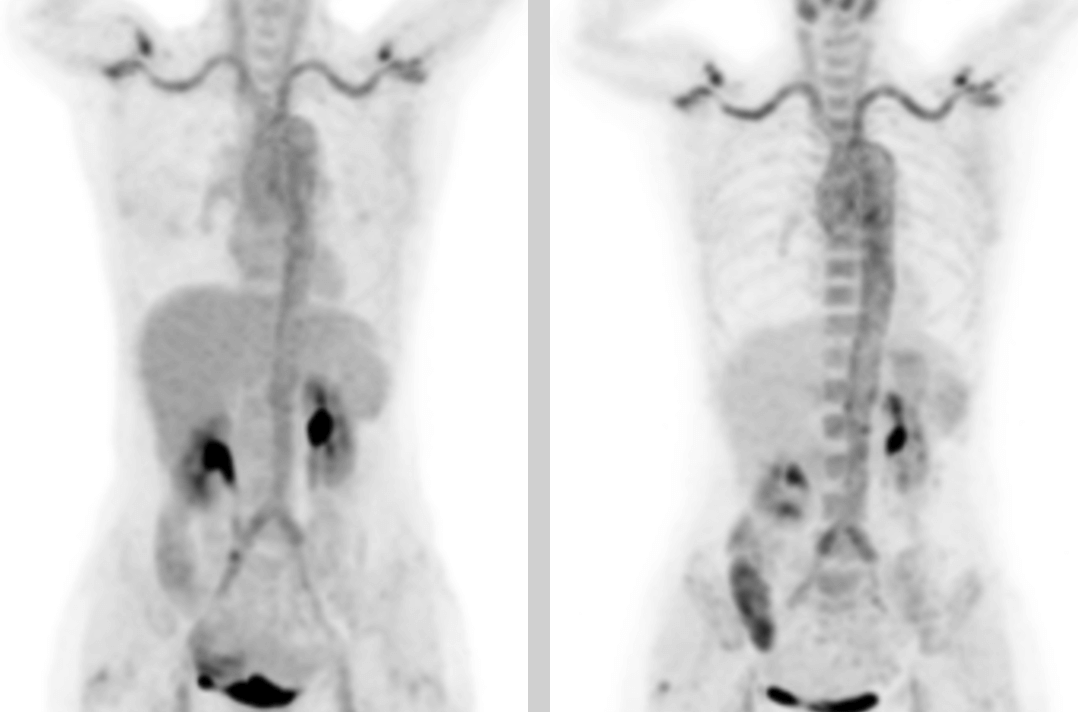

A 58-year-old women went to the hospital for intermittent fever for more than 40 days. Her highest body temperature was 38.9℃. Other symptoms included fatigue and shoulder joint pain which were especially acute in the afternoon and at night without cold, chills, sputum, hemoptysis, chest pain, chest tightness and shortness of breath. After two weeks of intravenous administration of "cephalosporin antibiotics" there was no improvement, and intermittent fever continued. The outpatient clinics noted the patient had "fever of unknown origin." There were no obvious diagnostic features upon physical examination. The results of a routine blood test were as follows: erythrocyte sedimentation rate in the first hour: 72mm; high-sensitivity C-reactive protein: 204. 20mg/l. Then, the patient had a whole-body F-FDG PET-CT examination to find the cause of the fever of unknown origin.

In the PET/CT images, wall thickening with increased glucose metabolism occurred in several parts of the body (bilateral internal carotid artery, common carotid artery, brachiocephalic trunk, bilateral subclavian and axillary arteries, thoracic aorta, abdominal aorta, bilateral common iliac artery, internal iliac artery, external iliac artery and femoral artery), which was considered to be caused by inflammatory changes. Combined with the patient’s medical history, clinical symptoms, examination and imaging findings, she was diagnosed with T.A. After standardized anti-inflammation treatment, her body temperature dropped and her condition improved.